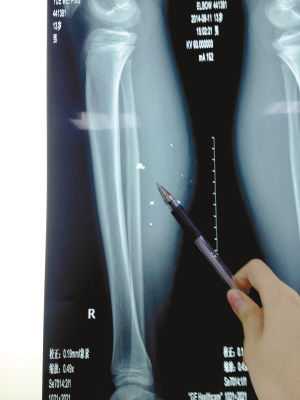

X光片顯示:手機(jī)電池內(nèi)的物質(zhì)被炸進(jìn)了小平的右小腿里

8月10日凌晨,小平轉(zhuǎn)院至重慶醫(yī)科大學(xué)附屬兒童醫(yī)院。小平的主治醫(yī)生骨科二病房周悅航醫(yī)生介紹,入院時(shí)小平右小腿腫脹,經(jīng)檢查,發(fā)現(xiàn)有爆炸傷伴異物殘留。傷口較深,約1.5厘米~2厘米,手機(jī)爆炸后進(jìn)入患兒小腿的異物約有10處。周悅航說(shuō),由于進(jìn)入皮膚的異物較多,已深入肌肉,且比較分散,最深的一塊貼近骨頭,可能需要多次手術(shù)。

另外,醫(yī)生擔(dān)心手機(jī)爆炸后金屬物進(jìn)入患兒體內(nèi)可能會(huì)對(duì)患兒肌肉造成損傷,所以需盡快手術(shù)。據(jù)悉,8月14日上午,小平將接受小腿爆炸傷清創(chuàng)與異物取出術(shù)。